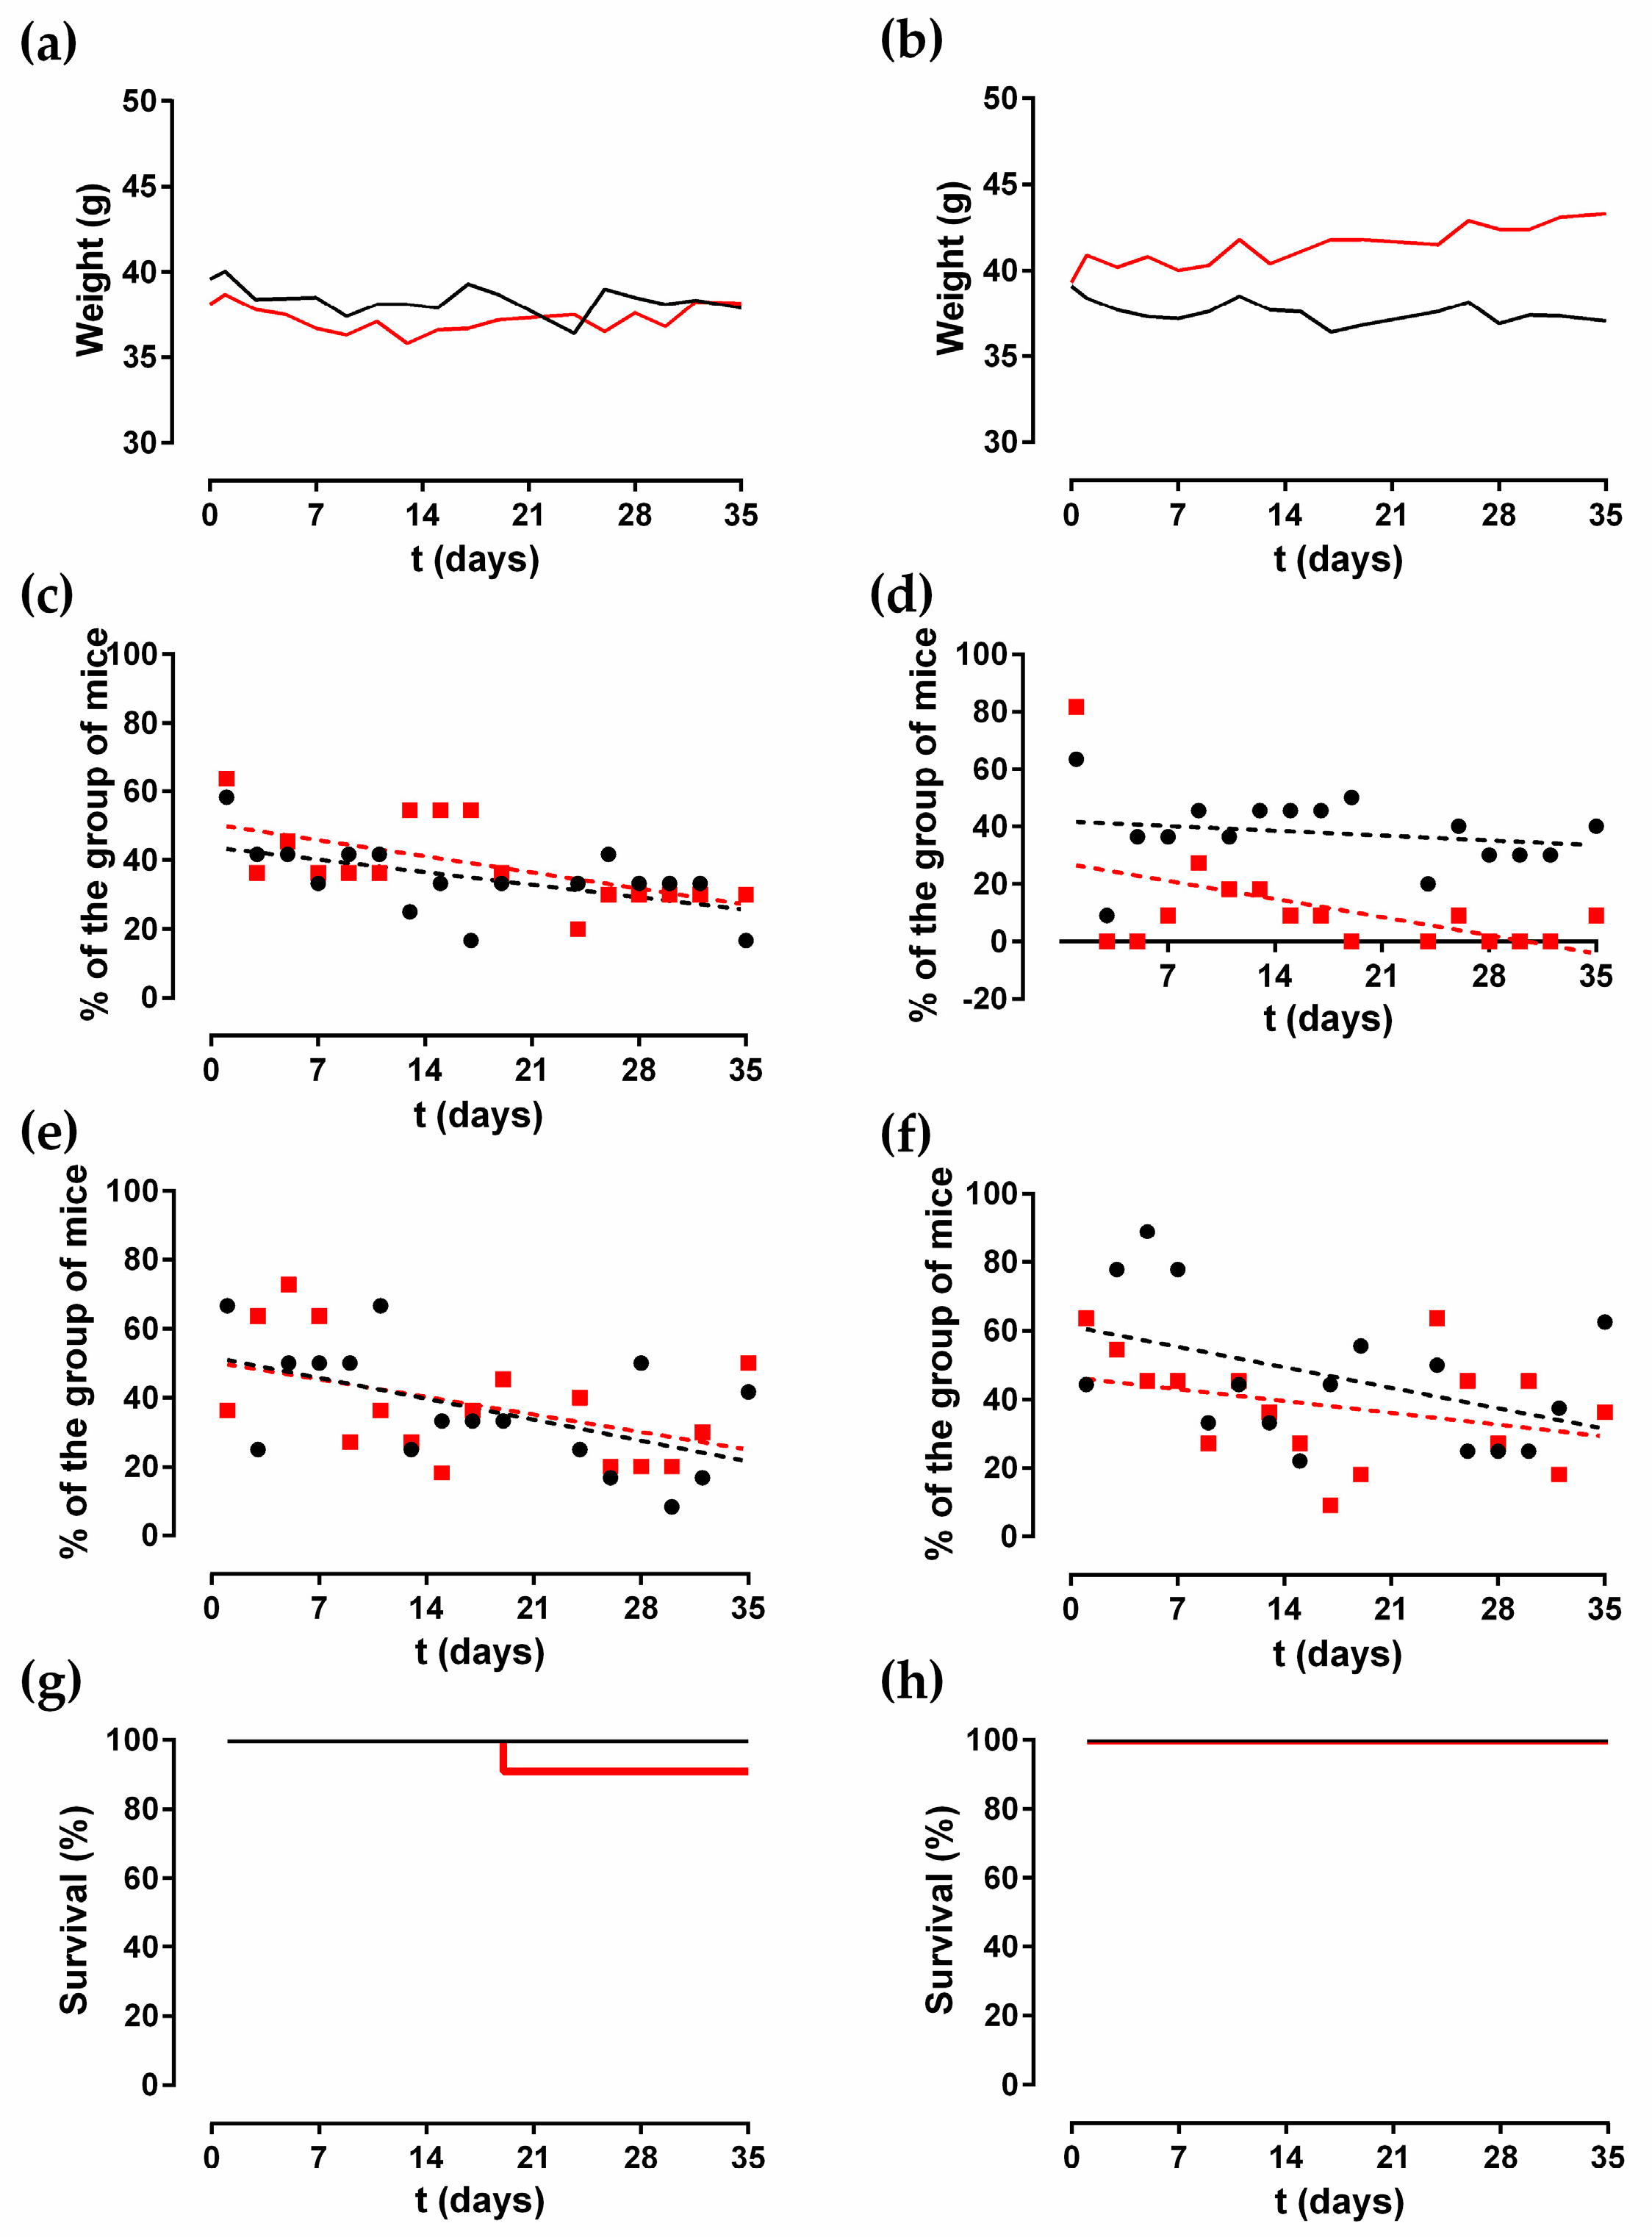

2.1. Animal Monitoring

4.2. Animal Surgical Model and Monitoring